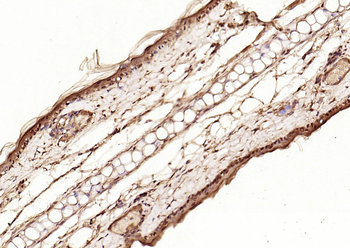

Phospho-Smad3 (Ser423 + Ser425) Rabbit Polyclonal Antibody [orb6983]

FC, IF, IHC-Fr, IHC-P, WB

Bovine, Canine, Equine, Gallus

Human, Mouse, Porcine, Rat

Rabbit

Polyclonal

Unconjugated

100 μl, 200 μl, 50 μlPhospho-SMAD5 (Ser463 + Ser465) Recombinant Rabbit Monoclonal Antibody [orb559123]